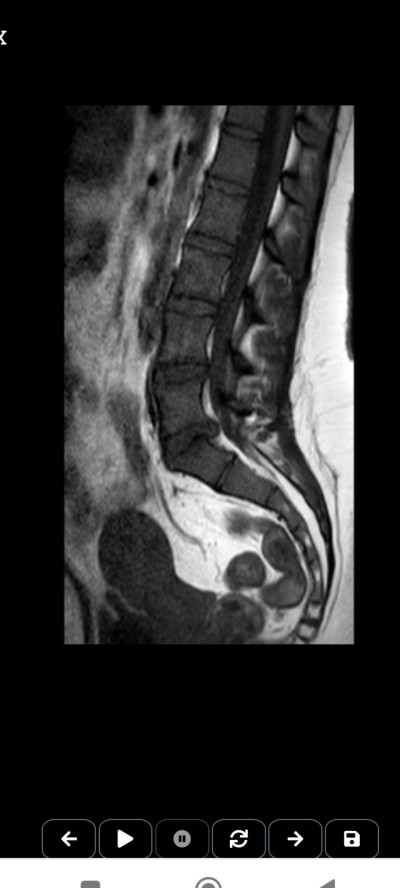

image

Baya büyük kitle var sanki baskı yapan

Alttaki beyaz yere doğru uzayani mi diyorsunuz bende onu gördüm

Tıbbi sekreterlik yaptım ama bende de boyun fıtığı ve omur ilik hemanjiomu var. Resim ekledim tekrar omur iliklerin bir tarafı düzgün sıralı diğer tarafları kabarık